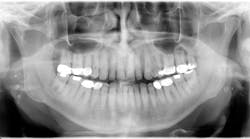

Tonsil stones are straightforward to diagnose. A visual exam, often aided by a tongue depressor, can reveal the presence of these calcifications in the tonsillar crypts.5

5. Babu BB, Tejasvi MLA, Avinash CK, Tonsillolith: a panoramic radiograph presentation. J Clin Diagn Res. 2013;7(10):2378-2379. doi:10.7860/JCDR/2013/5613.3530